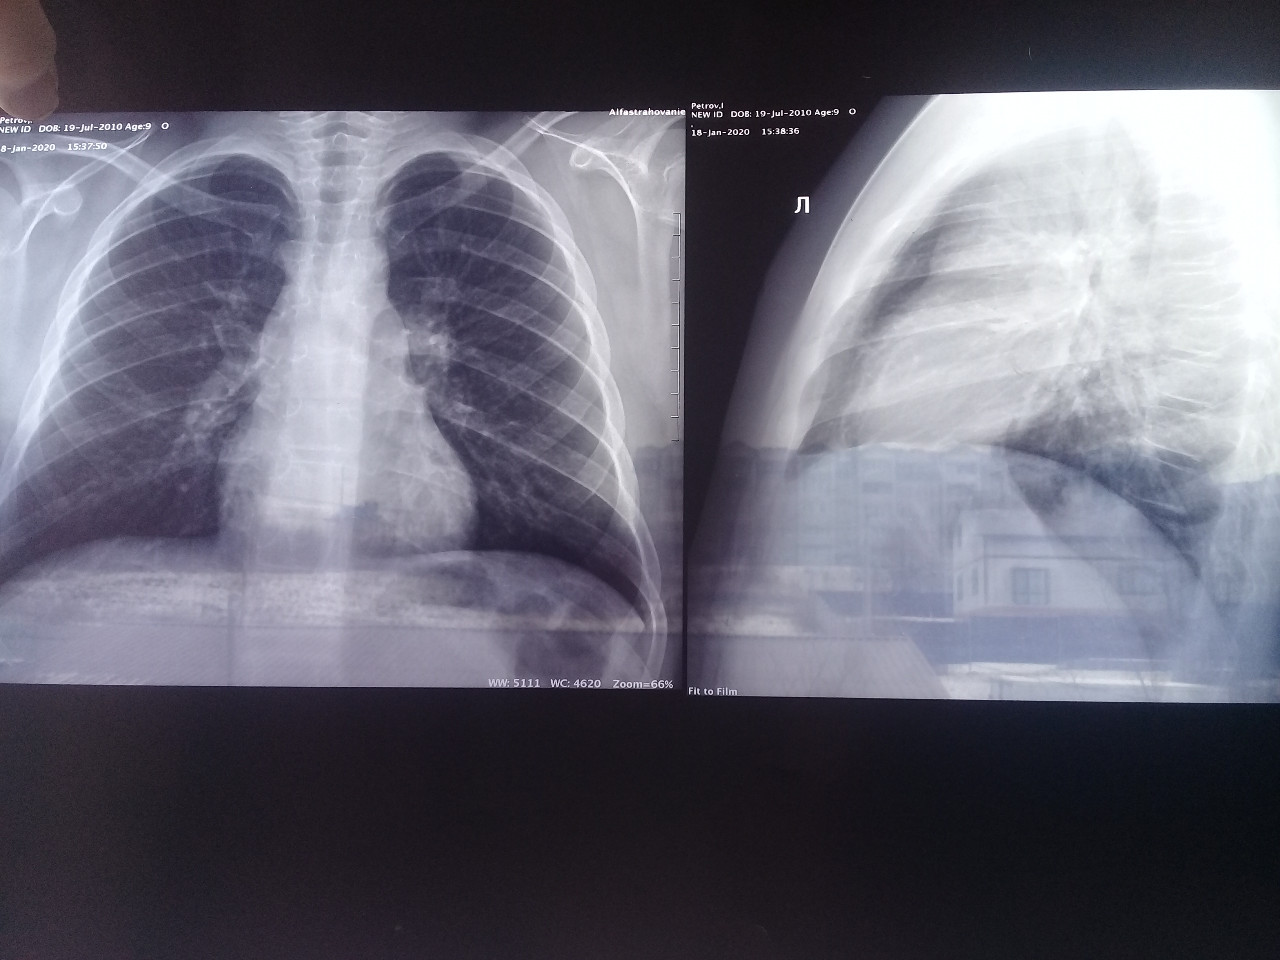

Рентгенодиагностика бронхопневмонии: Советы и примеры